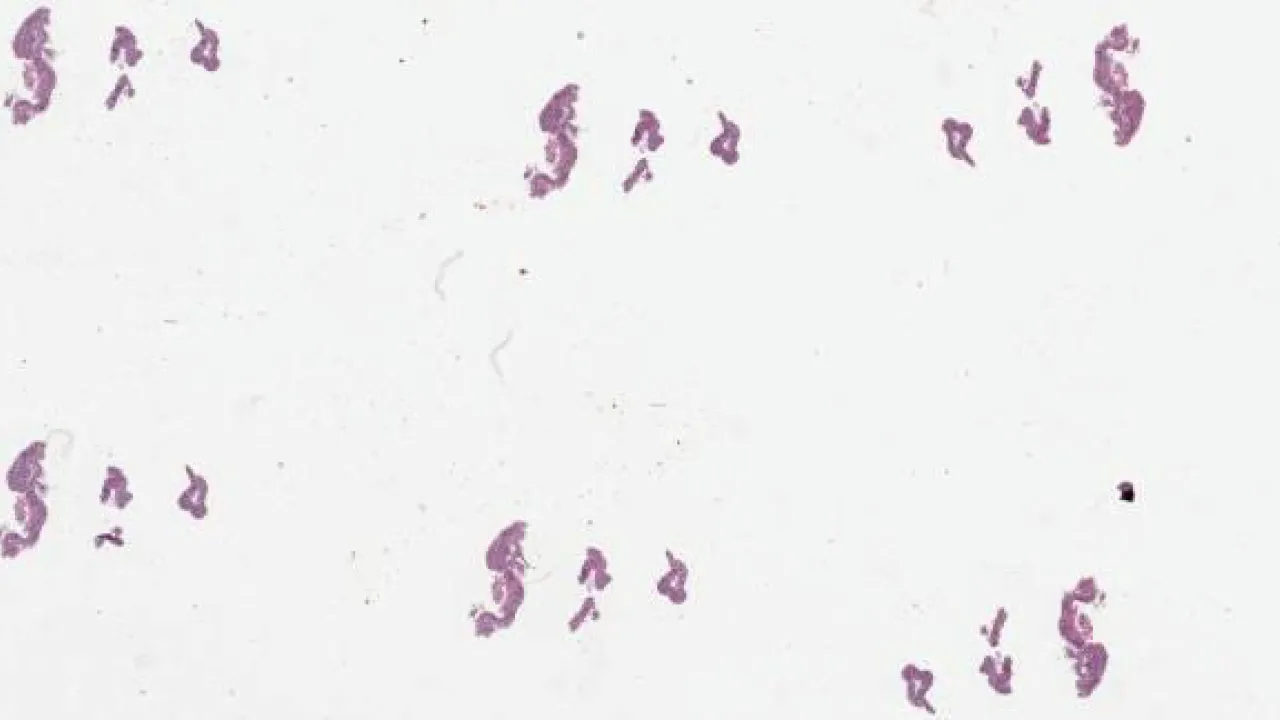

Colon, Amebiasis